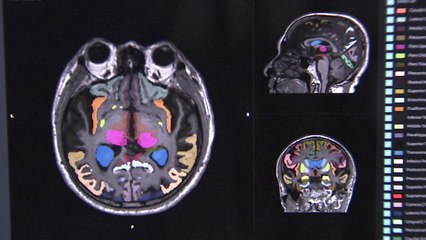

정부가 65세 이상 노인의 치매 실태를 조사한 결과 2023년 전체 노인의 치매 유병률은 9.25로 나타났습니다. br br 2016년 조사 때보다 0.25포인트 하락했지만, 여전히 100명 중 9명 넘게 치매를 앓고 있는 겁니다. br br 베이비붐 세대의 고령화로 올해 치매 환자는 97만 명을 웃돌고, br br 내년엔 처음으로 백만 명을 넘어, 19년 뒤인 2044년에 2백만 명을 돌파할 것으로 예상됩니다. br br 노인 혼자 살거나 교육 수준이 낮을수록 치매에 취약한 것으로 파악됐습니다. br br 또, 치매 환자와 동거하는 가족의 45.8는 돌봄에 부담을 느낀다고 토로했습니다. br br 치매 전 단계로 기억력과 언어능력 등이 크게 떨어졌지만, 일상생활은 가능한 경도인지장애는 더욱 심각합니다. br br 2016년보다 65세 이상 노인 유병률이 6포인트 넘게 급증해 28.42를 기록했습니다. br br 올해 경도인지장애 진단자는 무려 297만 명에 달하고, br br 내년에 3백만 명을 돌파해 2033년엔 4백만 명을 넘을 것으로 보입니다. br br 초고령 사회 진입에 따른 피할 수 없는 난제인데, br br 정부는 찾아가는 치매 검사와 장기요양 재가 서비스를 확대하는 등 지원 정책을 강화할 방침입니다. br br YTN 권민석입니다. br br 영상편집ㅣ윤용준 br 디자인ㅣ이가은 br 자막뉴스ㅣ이 선, 이도형 br br #YTN자막뉴스 br br br br ※ '당신의 제보가 뉴스가 됩니다' br [카카오톡] YTN 검색해 채널 추가 br [전화] 02-398-8585 br [메일] social@ytn.co.krbr br ▶ 기사 원문 : ▶ 제보 안내 : , 모바일앱, social@ytn.co.